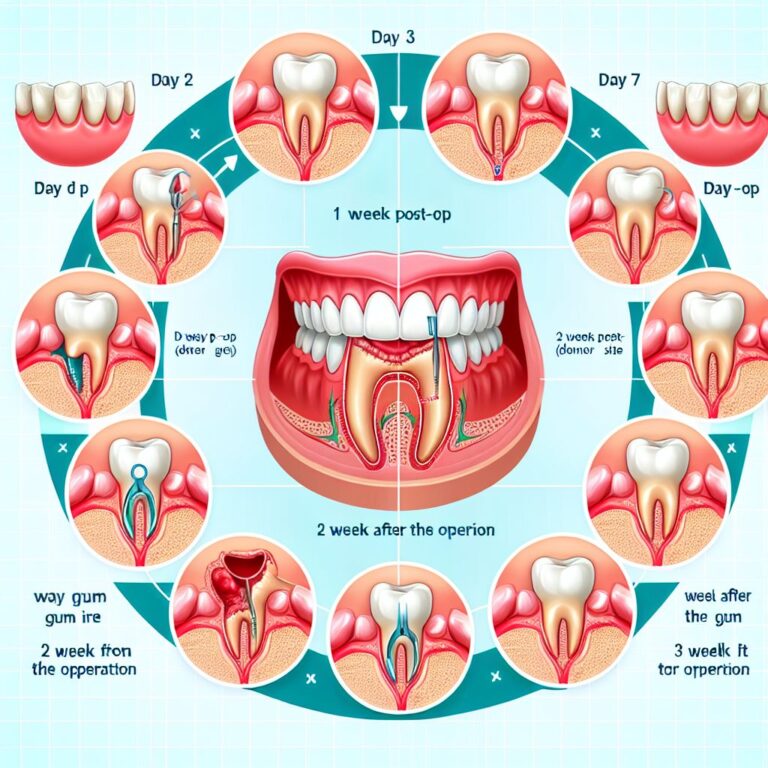

The palate (roof of your mouth) contains thick, fibrous tissue that closely resembles healthy gum tissue. During the harvesting procedure, your surgeon removes a small piece of this tissue, carefully selecting the appropriate thickness and size needed for your graft. The palatal donor site is then sutured and typically heals within 1-2 weeks. Modern techniques have significantly reduced discomfort associated with palatal harvesting, though you may experience some soreness similar to a pizza burn during the healing period.

When using your own tissue, periodontists employ two main techniques. Free gingival grafts involve taking all layers of the palatal tissue, including the visible outer layer (epithelium). This technique creates a patch of thicker tissue that looks somewhat different from surrounding gums initially but provides excellent protection. Connective tissue grafts, on the other hand, use only the deeper layer from beneath the surface, leaving the outer layer intact at the donor site. This method offers better esthetic results as the graft blends more naturally with surrounding tissue.

Recovery expectations and your ability to manage post-operative care factor into graft selection. Palatal harvesting requires careful attention to the donor site during healing. If you have a low pain threshold or concerns about managing two surgical sites, donor materials may be preferable. Your work schedule, upcoming events, and ability to follow post-operative instructions all influence the ideal approach for your specific situation.